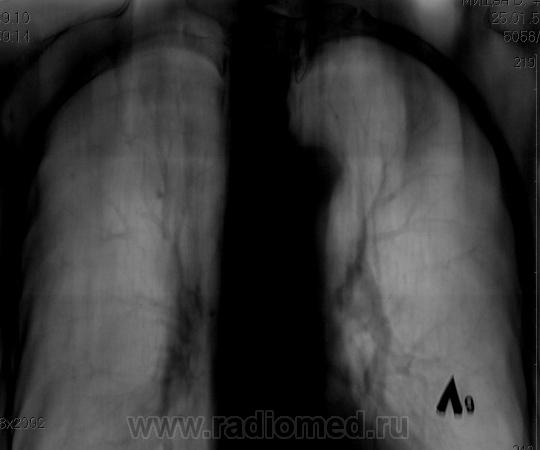

Справа на верхушке инфильтративная тень. Слева в задних отделах мелкие буллы.

На последнем срезе тень в 1 сегменте, мелкие полости в верхних долях с обеих сторон.